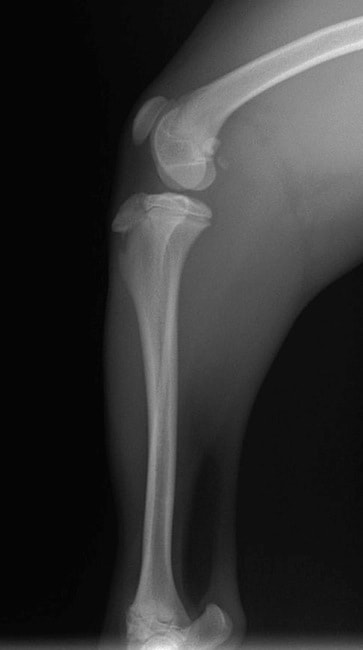

■ 症例24 キャバリア 7か月

左右膝蓋骨内方脱臼(左:グレードⅣ 右:グレードⅢ)

以前から左右後肢の跛行が認められ、整形外科学的検査・レントゲン検査により左右の膝蓋骨脱臼が認められた。症状が重度である左膝の膝蓋骨脱臼整復術を行った。外科手技は縫工筋及び内側広筋の解放、脛骨粗面の外側転位、滑車ブロック形造溝術、内外側関節方の縫縮を実施した。術後一か月時点で、左の膝蓋骨は安定しており経過は良好である。

本症例は成長期における重度の膝蓋骨脱臼であり、術後の再発の可能性もあるため、経過をしっかりと観察していく必要がある。また、今回手術を実施していない右膝に関しても経過を観察し、手術を検討していくこととする。